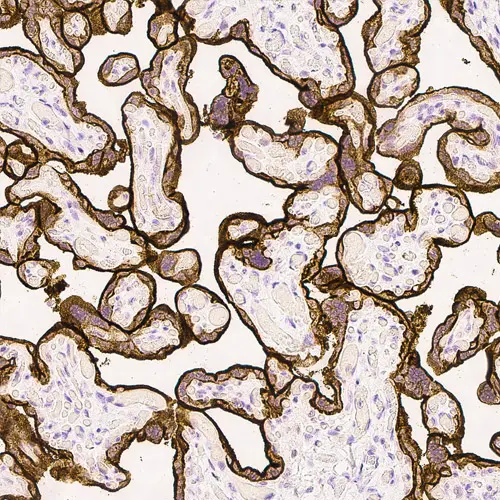

Human placenta: immunohistochemical staining for Epidermal Growth Factor Receptor. High expression of EGFR localized in the trophoblastic layer of the placental villi. Epidermal Growth Factor Receptor: clone EGFR.113

Epidermal Growth Factor Receptor (EGFR) is a transmembrane protein receptor of 170 kD with tyrosine kinase activity. Increased levels of EGFR are reported to be linked with malignant transformation of squamous cells e.g., in squamous cell carcinoma of the lung, head, neck, skin, cervix and esophagus. EGFR may also play a role in the development and progression of hepatocellular carcinomas where recurrence rates are higher in EGFR-positive cases. This correlation has similarly been reported in colorectal cancers where EGFR, produced by tumor cells, plays an important role in the invasiveness and proliferation of colorectal cancers. The majority of published studies of EGFR expression in human breast cancer has similarly shown an association with EGFR expression where it is inversely related to estrogen receptor status.

Clone EGFR.113 is raised to the extracellular domain of the EGFR molecule.